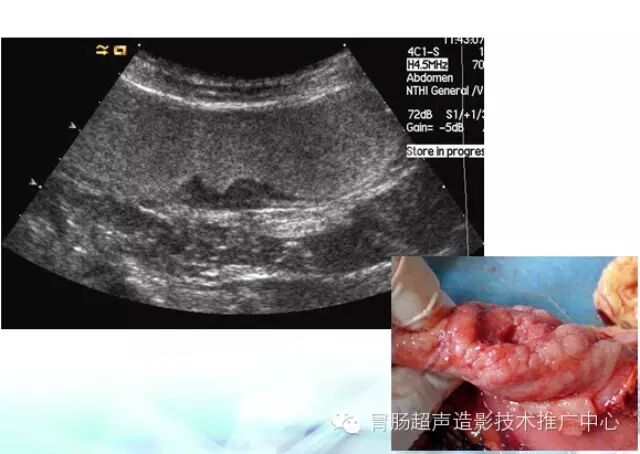

慢性浅表性胃炎是慢性胃炎中最常见的类型,临床检出率达80%-90%。

在一些医院,只要你接受胃肠检查,几乎无一例外会得到这么一个最轻级别的诊断:慢性浅表性胃炎。特别是胃镜检查;临床医师很难见到“胃、十二指肠未见异常”的正常胃镜报告。事实上,胃肠检查报告中的很多慢性浅表性胃炎,只是功能性消化不良或非溃疡性消化不良,并不是胃黏膜真的有了慢性炎症。它反映了胃粘膜浅层有淋巴细胞或浆细胞浸润,而深层的胃腺体正常。根据炎症细胞浸润程度,浅表性胃炎可分为轻型、中型、或伴急性活动等类型。根据情况不同,使用不同药物后患者可治愈。